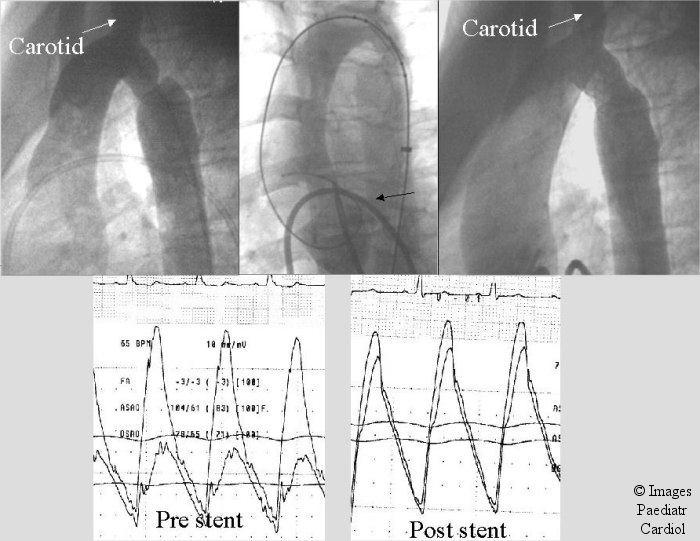

Balloon expandable stents have been used to manage coarctation of the aorta in selected patients with very encouraging results. After the successful use of the Palmaz stents in these lesions newer stents as well as modifications of the Palmaz stents have been introduced to achieve optimal results in these patients. In this review, the older as well as the newer type stents used in coarctation are discussed. Technical considerations to achieve successful stent implantation and choice is outlined.

球囊扩张式支架已被用于治疗部分主动脉缩窄患者,效果非常令人鼓舞。在成功将帕尔马兹支架用于这些病变后,已引入了更新型的支架以及帕尔马兹支架的改良型,以便在这些患者中取得最佳效果。在这篇综述中,将讨论用于主动脉缩窄的老式和新型支架。概述了实现成功支架植入的技术要点及选择。